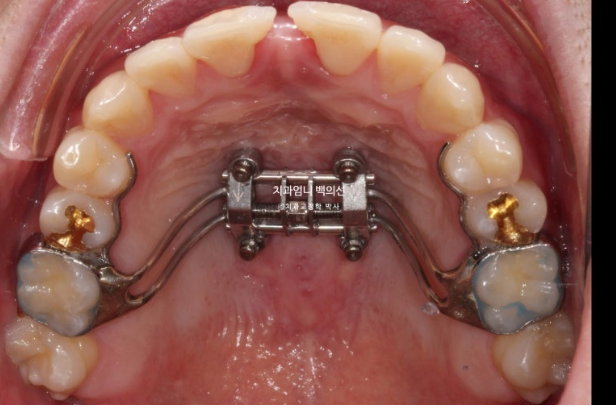

At our clinic, we use a palatal expansion device with miniscrews only for adults who truly need expansion of the palate.

After attempting arch expansion with an MSE palatal expander, we planned to resolve the open bite and crossbite with Invisalign.

First, we needed to expand the arch.

23.01

This is what it looked like in January 2023, one month after the initial visit, with the expansion device in place.

Expansion began in January 2023, and in February, although the suture had not yet opened, the expansion device could no longer turn. A minor procedure called corticopuncture was performed to actively promote separation of the palatal suture.